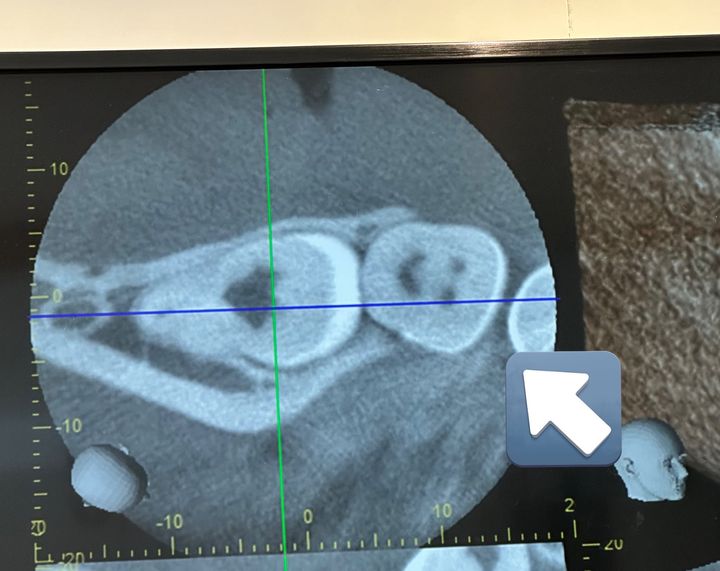

私は親知らずのCT撮ったらニコちゃんうつってました

先生に「初めて見たwwww」

って笑われました

投稿者さんは検査を終えたの画像を見てびっくり!なんと一番奥の歯「親知らず」に、「ニコちゃんマーク」が描かれているように見えたのです。

何かしらの影が写り込んだのでしょうが、歯がにっこり微笑んでいるようでとても可愛いですね。

「私も専門的なことはわからないのですが、ニコちゃんマークに見えるのはいわゆる『歯根菅』と言われる歯の根っこらしいです!真上からのCTを撮ることで、CTに写った影が運良くはっきりとニコちゃんマークに見えたみたいです